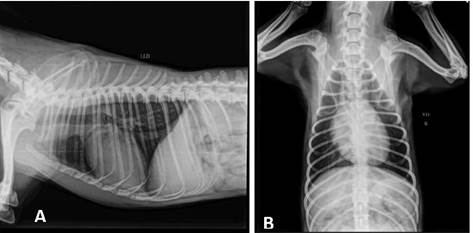

According to the history and clinical findings, the diagnosis of perineal hernia was established, which may be secondary to prostatic alteration, evident on ultrasound. The suggestion was to perform an orchiectomy surgery, with the aim of possible treatment for the reduction of the prostate and surgical correction of perineal hernia. After accepting the surgical procedure, the owner brought the animal for preoperative examinations. On physical examination, the mucous membranes were of normal color, adequate hydration, no pain on abdominal palpation, NDN lymph nodes (nothing noteworthy), left unilateral perineal hernia. The pre-surgical complementary tests performed were blood count, urea, creatinine, ALT, AST, GGT, AF, electrocardiogram and chest x-ray. (LL/ VD) (figure 2). The owner was informed about the possibility of recurrence that after the surgical procedure.